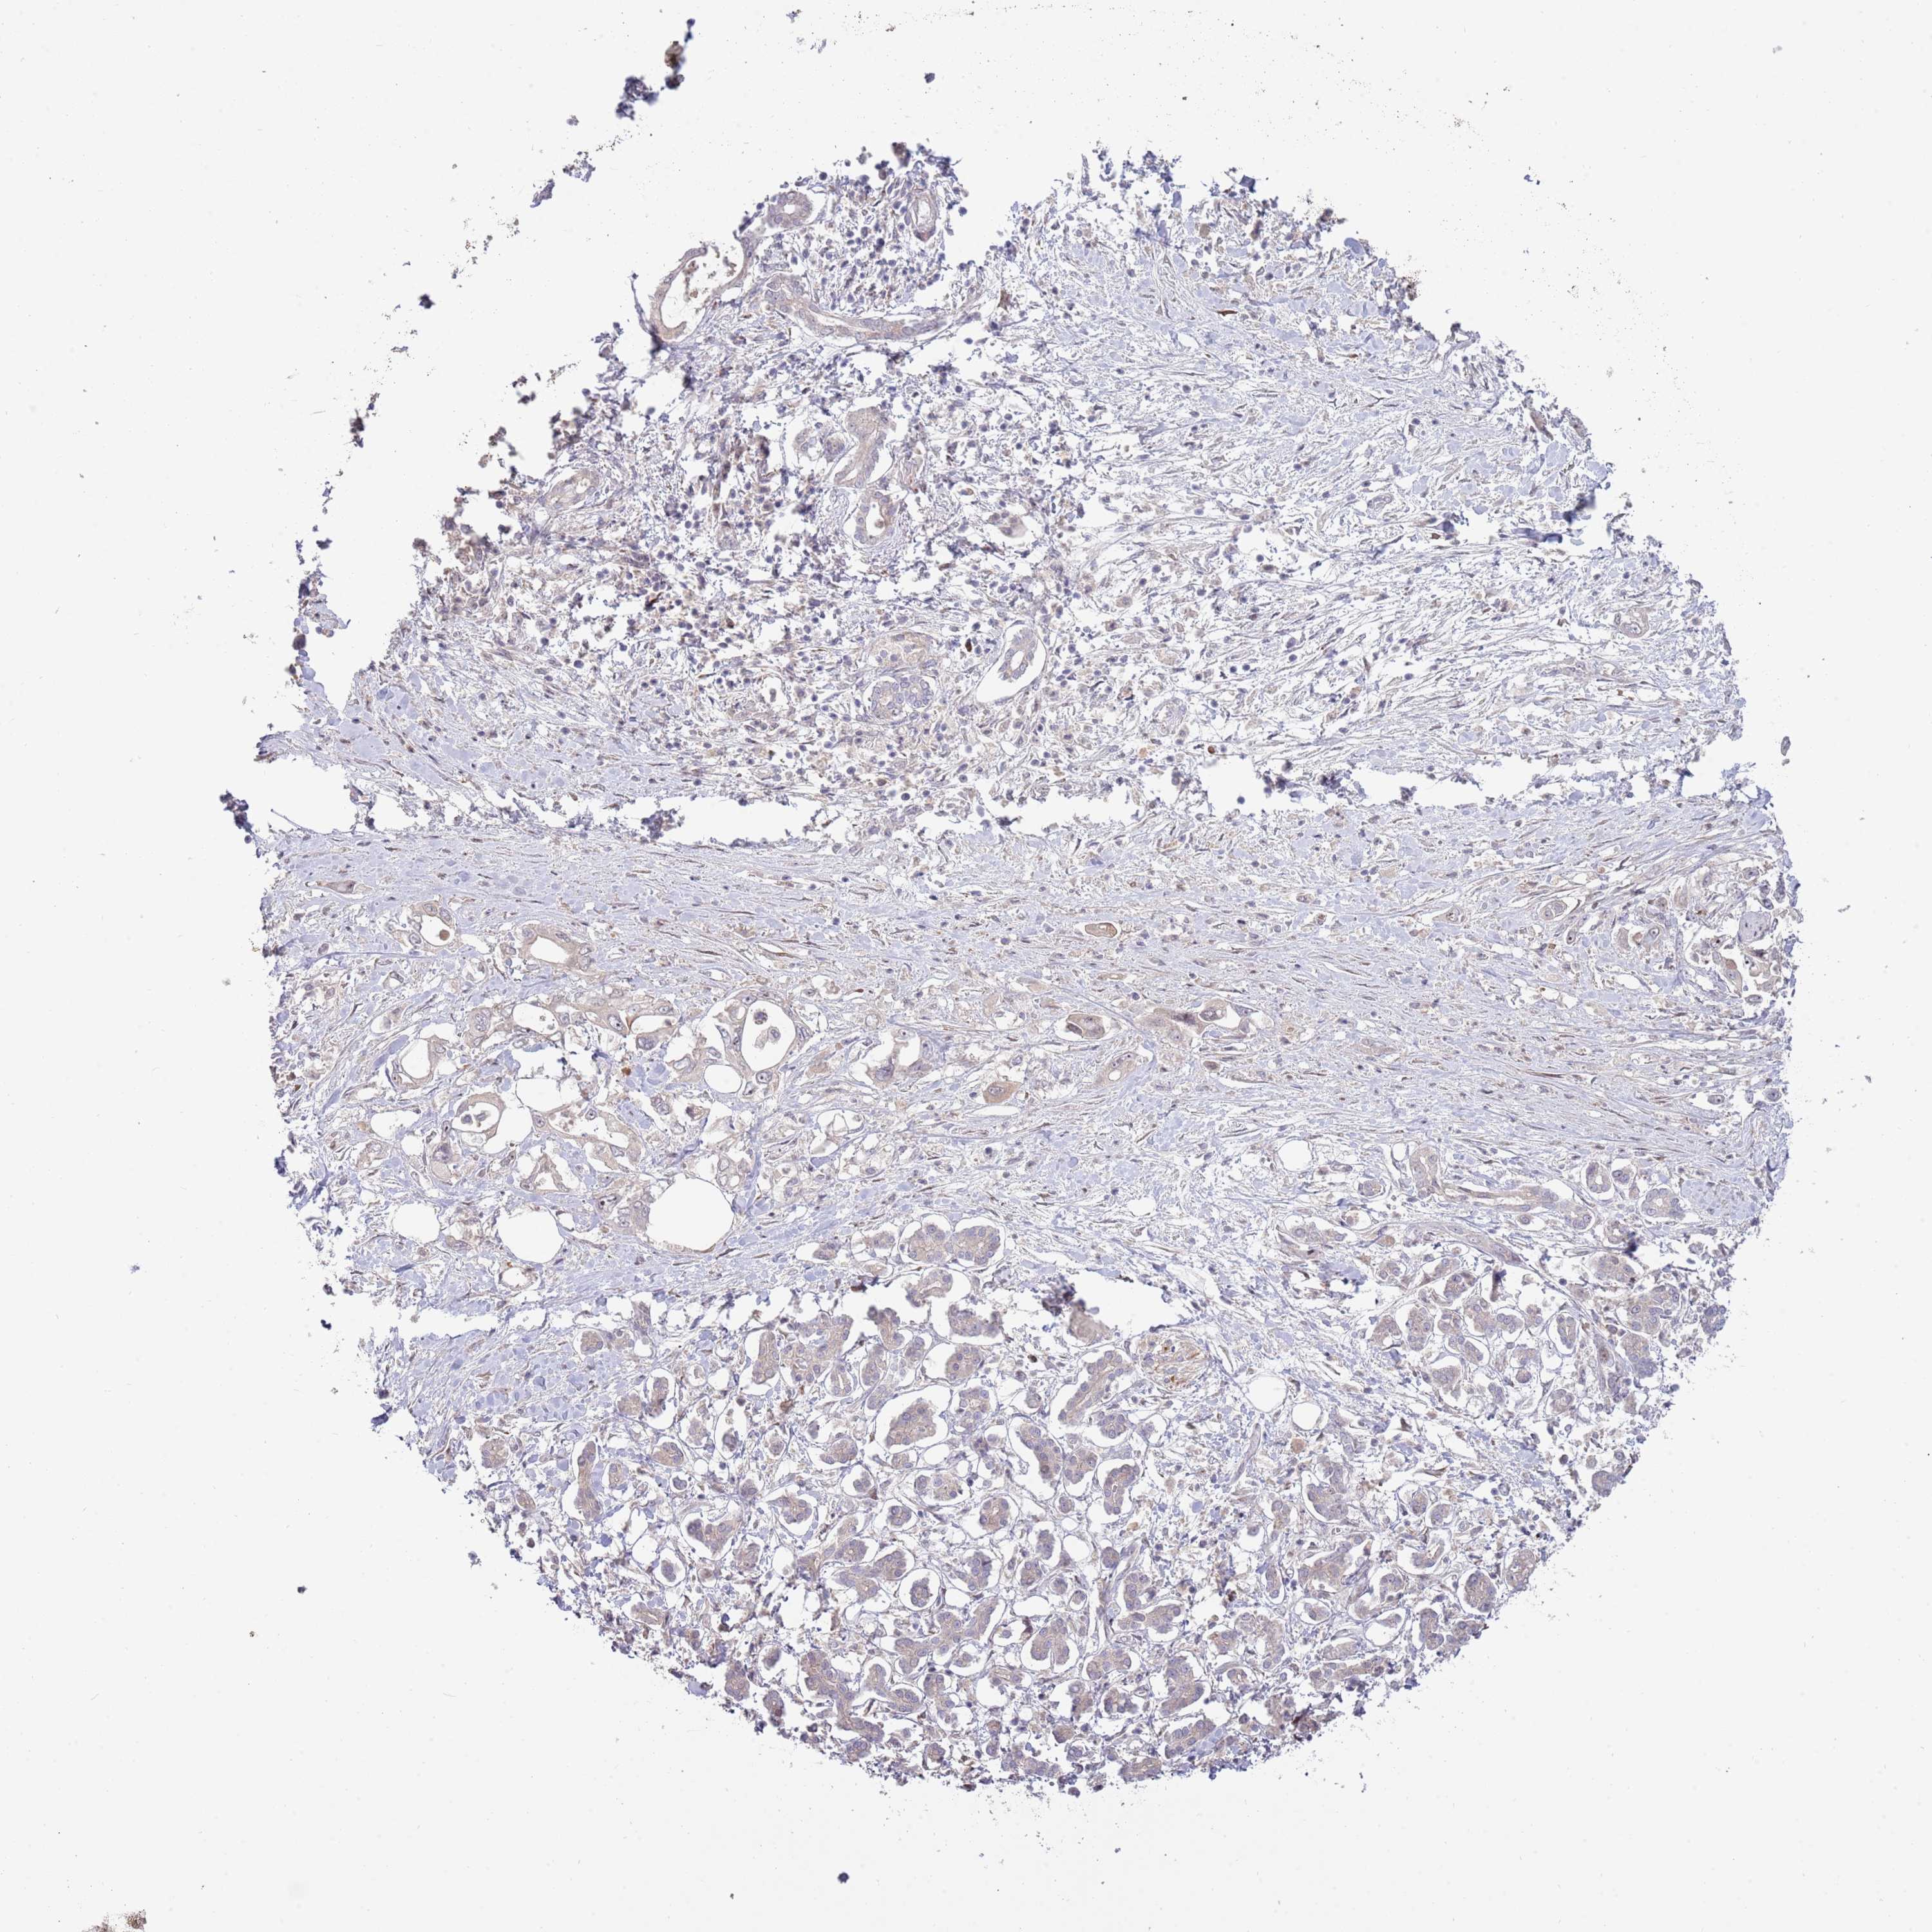

PANCREATIC CANCER - Protein expressioni

A mouse-over function shows sample information and annotation data. Click on an image to view it in a full screen mode. Samples can be filtered based on level of antibody staining by selecting one or several of the following categories: high, medium, low and not detected. The assay and annotation is described here.

Note that samples used for immunohistochemistry by the Human Protein Atlas do not correspond to samples in the TCGA dataset.

Antibody stainingi

Antibody staining in the annotated cell types in the current human tissue is reported as not detected, low, medium, or high, based on conventional immunohistochemistry profiling in selected tissues. This score is based on the combination of the staining intensity and fraction of stained cells.

Each image is clickable and will lead to virtual microscopy that enables deeper exploration of all samples and also displays staining intensity scores, fraction scores and subcellular localization as well as patient and tissue information for each sample.

Antibody HPA042594

Antibody HPA048487

Adenocarcinoma, NOS